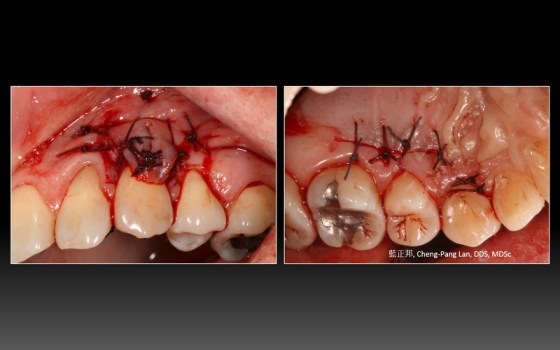

Recipient Site: Harris’s technique, 1992

Donor Site: Bruno’s technique, 1994